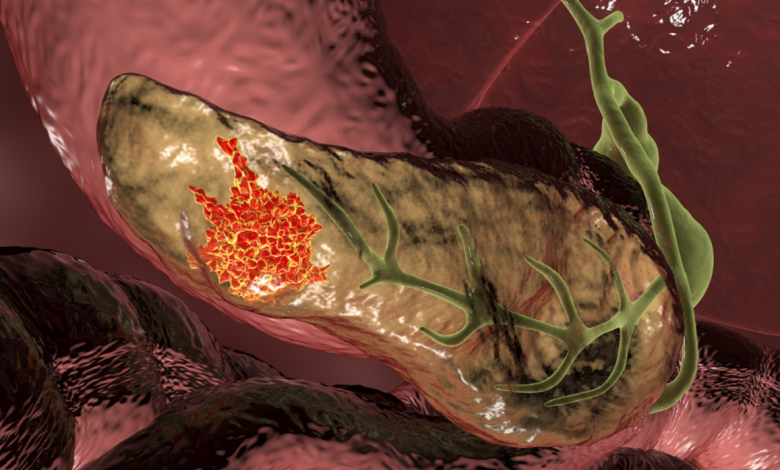

حقق فريق من الباحثين من جامعة كوبنهاغن وRigshospitalet تقدما كبيرا في تطوير علاج مبتكر لسرطان البنكرياس، أحد أكثر أنواع السرطان فتكا.

استخدم الباحثون تقنية “مقترنات الأدوية المضادة” (ADC) لعلاج سرطان البنكرياس. وهذه التقنية كانت قد أثبتت فاعليتها سابقا في علاج أنواع أخرى من السرطان، ووجدت الدراسة الآن تطبيقا جديدا لها لمكافحة سرطان البنكرياس القاتل.

وأوضح لارس هينينغ إنغلهولم، المعد المشارك للدراسة، أن العلاج يعتمد على تدمير الخلايا السرطانية والخلايا الداعمة التي تساعد السرطان على النمو وحمايته. كما يساهم هذا العلاج في تحفيز جهاز المناعة لمهاجمة الورم بشكل فعال.

ويعتمد العلاج على 3 مكونات رئيسية هي: جسم مضاد ورابط كيميائي (يربط الجسم المضاد بالدواء) ودواء كيميائي قوي. فعندما يدخل الجسم المضاد إلى الخلايا السرطانية، يُطلق العلاج الكيميائي الذي يقتل الخلايا السرطانية من الداخل دون التأثير على الخلايا السليمة.